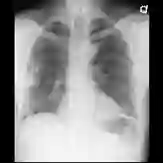

Despite the progress in utilizing deep learning to automate chest radiograph interpretation and disease diagnosis tasks, change between sequential Chest X-rays (CXRs) has received limited attention. Monitoring the progression of pathologies that are visualized through chest imaging poses several challenges in anatomical motion estimation and image registration, i.e., spatially aligning the two images and modeling temporal dynamics in change detection. In this work, we propose CheXRelNet, a neural model that can track longitudinal pathology change relations between two CXRs. CheXRelNet incorporates local and global visual features, utilizes inter-image and intra-image anatomical information, and learns dependencies between anatomical region attributes, to accurately predict disease change for a pair of CXRs. Experimental results on the Chest ImaGenome dataset show increased downstream performance compared to baselines. Code is available at https://github.com/PLAN-Lab/ChexRelNet